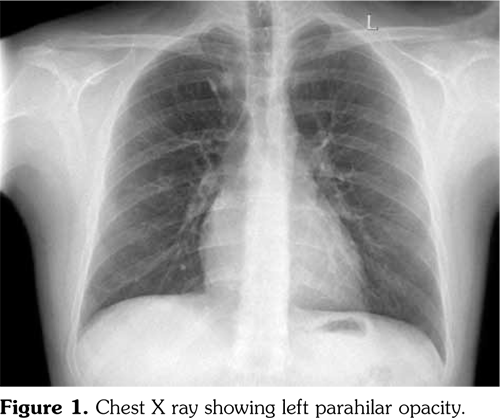

Chest X-ray showed left parahilar opacity (Figure 1). Pulmonary computed tomography (CT) angiogram revealed PAA with thrombus (Figure 2a). Bronchoscopy revealed no origin of bleeding. Echocardiography demonstrated mobile thrombus in the right ventricle (Figure 3a). Blood and urine cultures were sterile. Venereal Disease Research Laboratory test, tuberculosis tests, human immunodeficiency virus serology, antiphospholipid antibodies, anti-nuclear antibodies, and anti-neutrophil cytoplasmic antibodies were negative. Hereditary coagulation thrombophilic factors were normal.